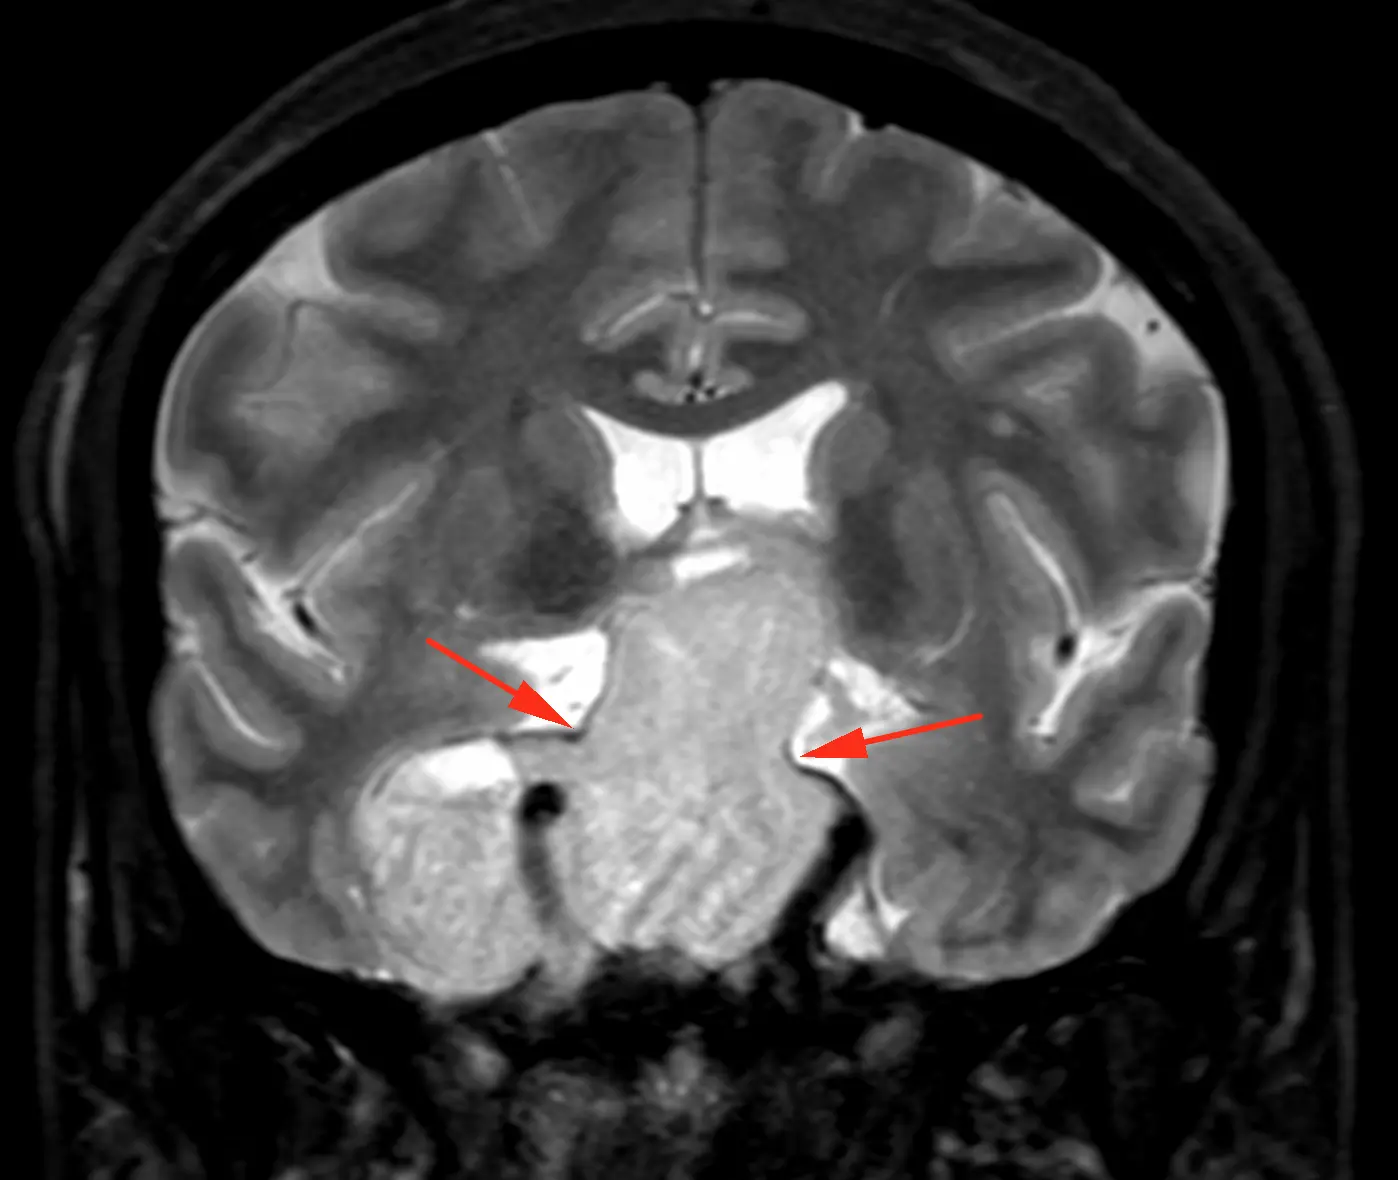

Наконец-то я увидел это воочию! Киста полости Верги, промежуточного паруса, осложнённая гидроцефалией. Из анамнеза: Низкое артериальнео давление, нарушение речи, затуманенное сознание, головная боль, головокружение, в 1989 году перенёс менингит.

А Вы видали такое? Я впервые вижу, раньше только читал в литературе.